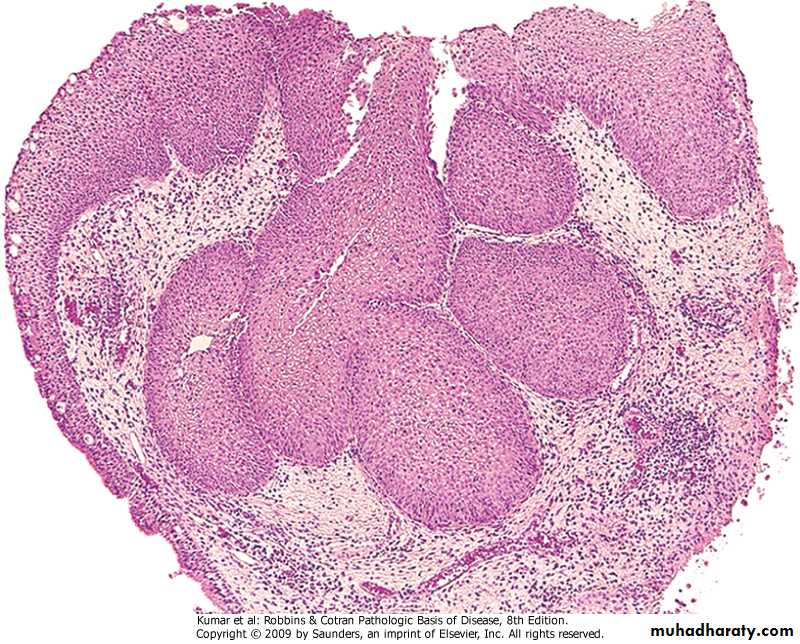

Bronchogenic carcinoma

Sequence of changes in bronchial epithelium

Squamous cell carcinoma of bronchus